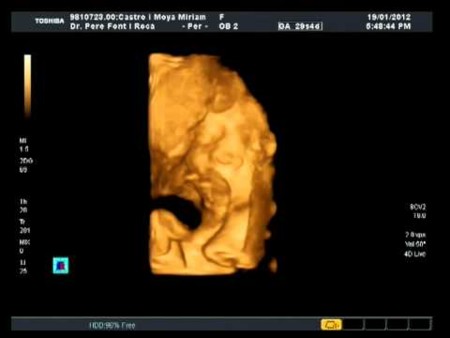

Estuvimos en el ginecólogo hace escasos días y, aunque tengo grabada la ecografía, no hay mucho que ver, básicamente porque a estas alturas de la película son ya tan grandes que sólo se ven porciones de partes del cuerpo y, en general, se ve poca cosa. Así que el vídeo que tenéis aquí arriba es la ecografía que le hicieron hace cosa de un mes, donde se le puede ver un poco la cara en 4D (lo hizo el ginecólogo por iniciativa propia y Guim decidió taparse la boca con el cordón…).